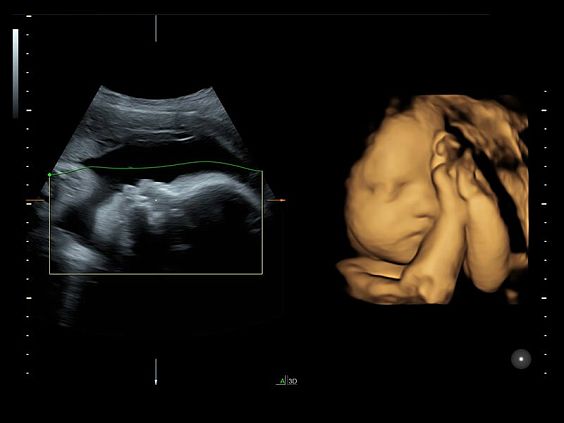

Клинические изображения

- 3D/4D Activation:

- Режим 3D.

- Режим 4D Realtime.

- SonoRenderlive – автоматическое определение границ конечностей и лица плода и получение объемного изображения в 3D/4D.

- Уверенность в диагнозе благодаря превосходному качеству 2D- и 3D-изображений.

- Исключительный анатомический реализм благодаря технологии HDlive при исследованиях в 3D- и 4D-режимах.

- Легкое получение 3D/4D-изображений с использованием технологии SonoRenderlive, автоматически изменяющей положение плоскости визуализации в зависимости от движений плода.